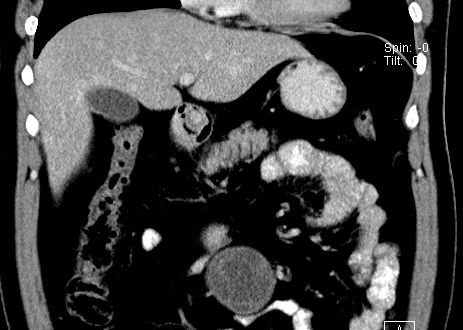

(腹腔)神经鞘瘤

男,48岁,间断性下腹不适1年。

手术探查

:距回盲部28厘米处肠系膜根部可见5*7cm左右包块,质中等硬度,活动度尚可,肝、胆、胰、脾肾未见明显异常。

病理

:(腹腔)

神经鞘瘤

,伴出血、坏死及囊性变,伴淋巴结反应性增生。

免疫组化结果

:sma(-), desmin(-), cd117(-), s-100(+++), nf(-),vimentin(+++).